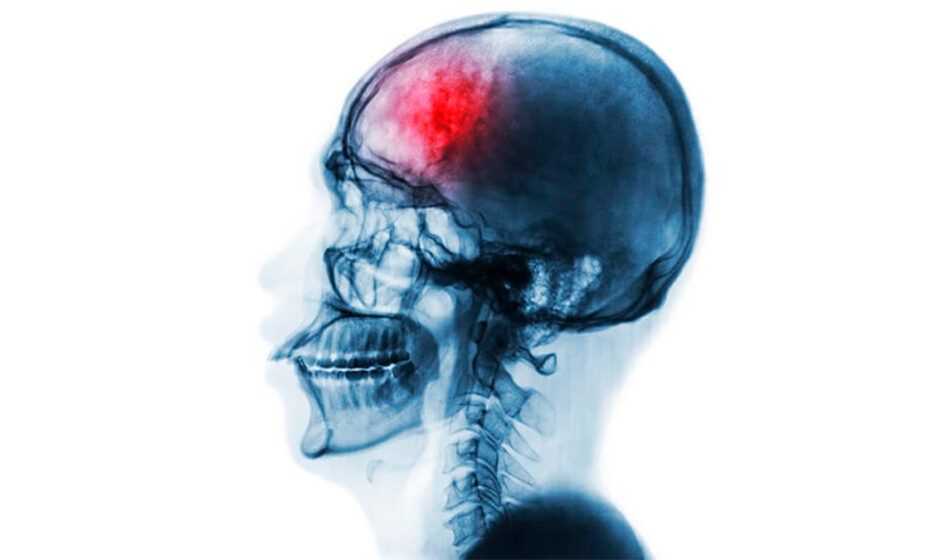

El estrés crónico puede dañar el cerebro y aumentar el riesgo de sufrir un accidente cerebrovascular

De acuerdo con especialistas de la Mayo Clinic y Banner Health, el estrés crónico puede alterar el funcionamiento del cerebro y del sistema circulatorio, incrementando el riesgo de sufrir un accidente cerebrovascular (ACV) —también conocido como derrame cerebral—, una emergencia médica que requiere atención inmediata.

Un accidente cerebrovascular ocurre cuando el flujo sanguíneo hacia el cerebro se reduce o se interrumpe. Sin oxígeno ni nutrientes, las células cerebrales comienzan a dañarse o mueren, lo que puede dejar secuelas permanentes o incluso provocar la muerte.